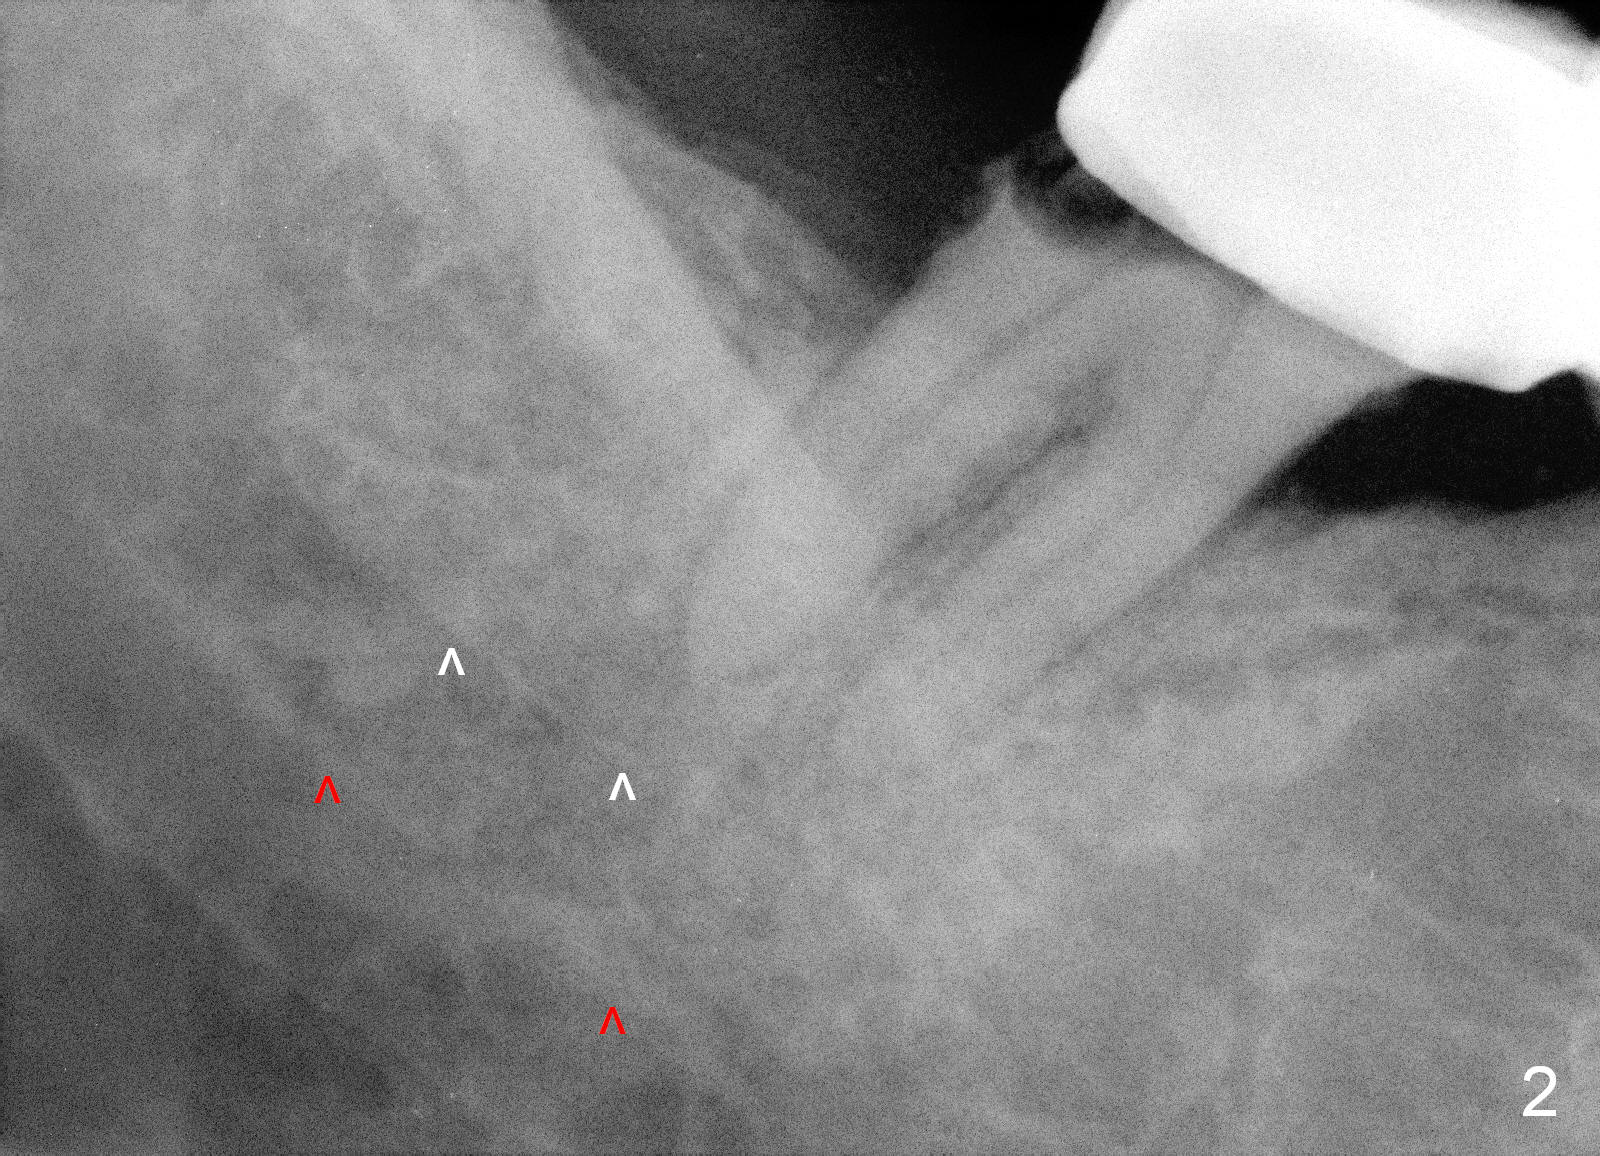

As to the depth of the osteotomy at the site of #31, it is difficult to differentiate the upper border of the Inferior Alveolar Canal (white vs. red arrowheads in Fig.2).

Therefore, it is safer to place an implant coronal to the white arrowheads, i.e., 2 mm apical to the apex of the mesial socket (compare Fig.2,3).